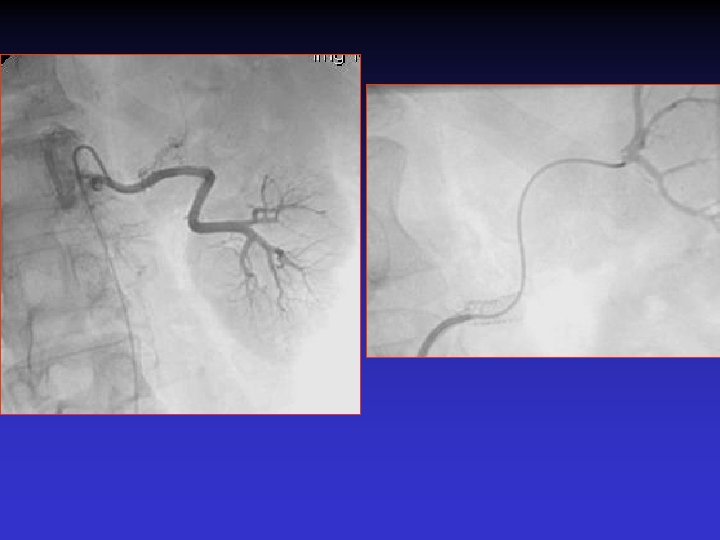

Case # 2 • 50 -year-old male with solitary kidney. • Smoker. • Refractory HTN. • Cr: 3. 8 mg/dl

• B/P: 160/80 mm. Hg • Cr: 1. 8 mg/dl

The patient was re-admitted 18 months later with Cr: 2. 8 mg/dl, and BP: 180/90 mm. Hg.